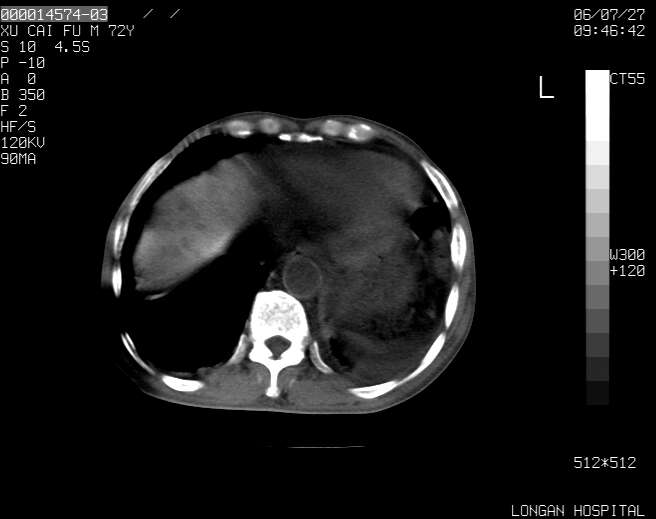

以下是引用winter在2006-7-30 20:14:00的发言:[br]1、考虑胆囊癌伴胆道侵犯并高位胆道梗阻、肝内多发转移、腹膜后淋巴结转移。[br]2、右肾轻度积水。[br]3、老人家72岁了胰腺头体尾部均较饱满,不过未见密度异常及其他异常征象。[br]4、腹水。

以下是引用jiajie在2006-7-31 7:10:00的发言:[br]考虑肝转移瘤,腹膜后淋巴结增大。[br]胃癌不能除外,建议胃镜检查。